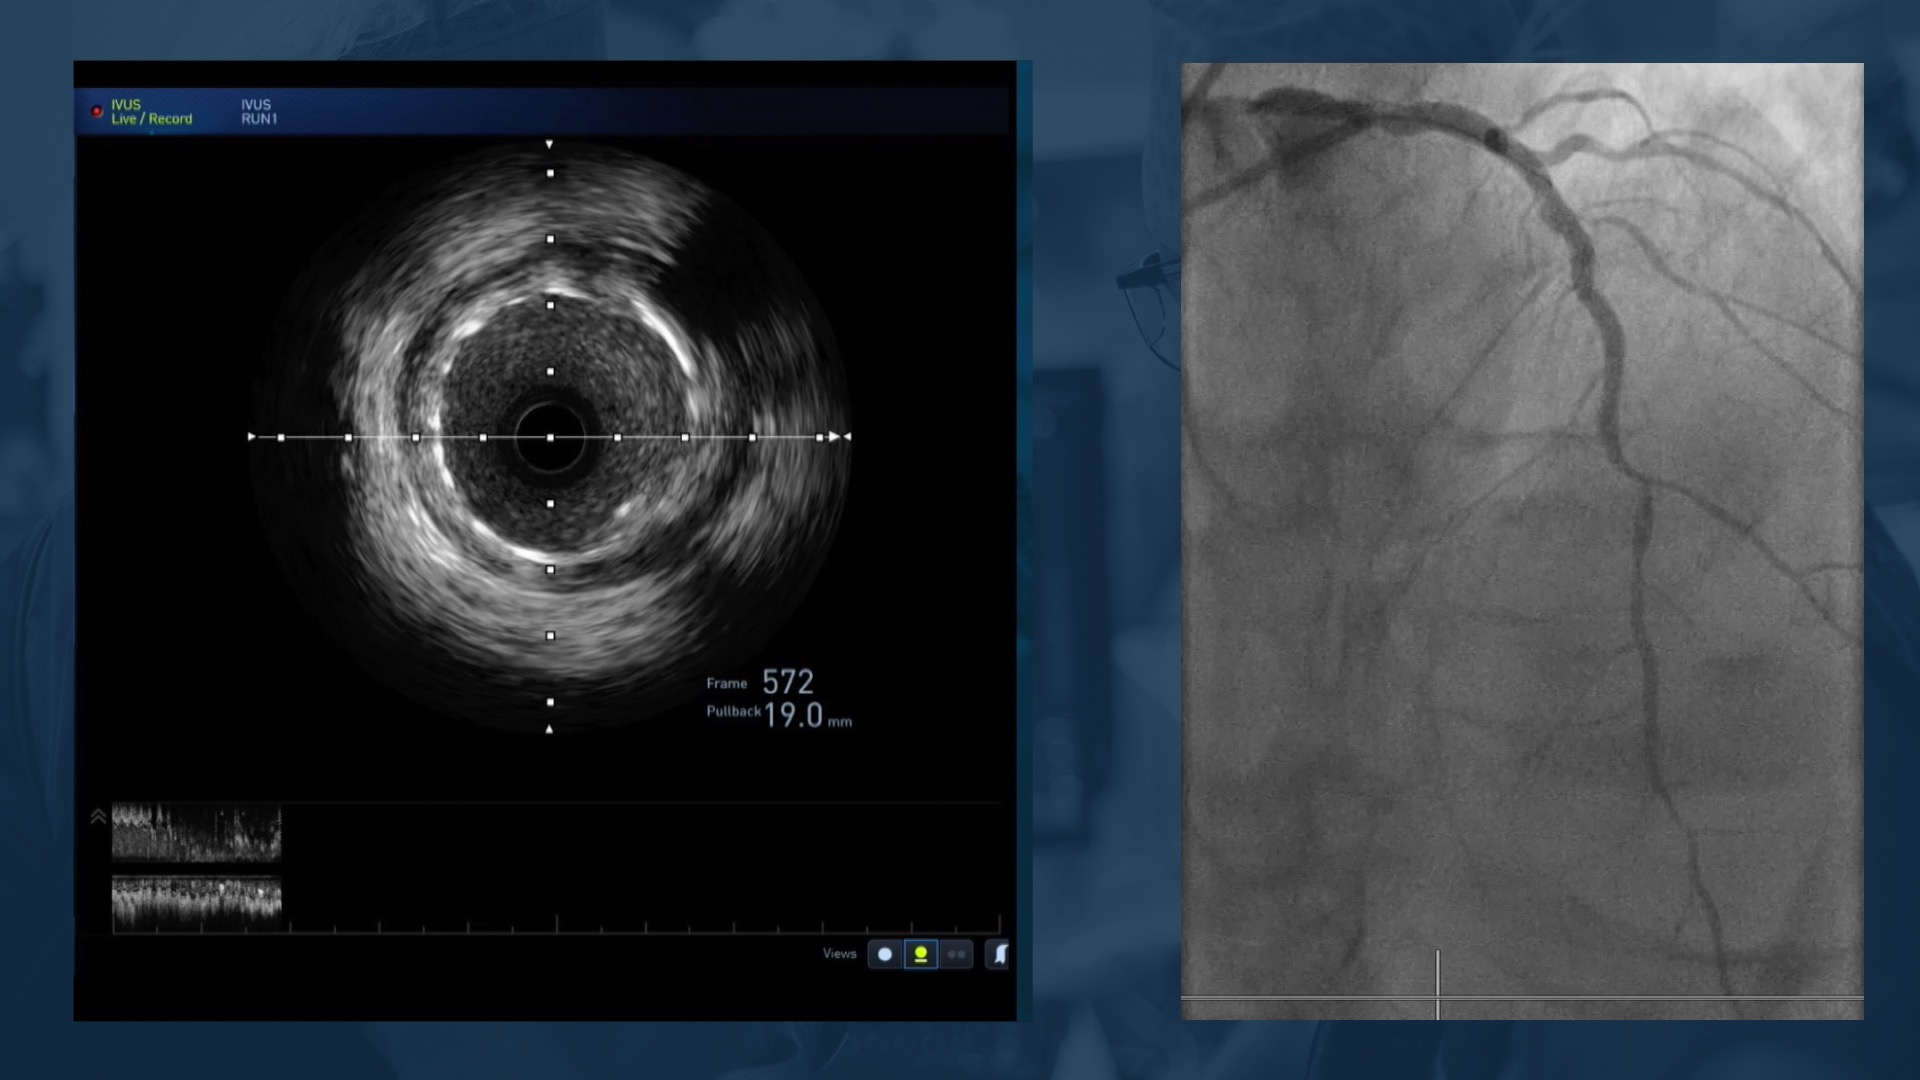

•Possible need for IVUS